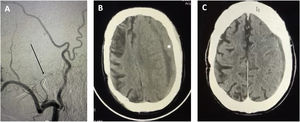

Furthermore, Gelabert et al., perhaps due to lack of knowledge of the current literature and despite the references provided, disagree with our idea that endovascular embolisation of the MMA may be performed under mild sedation. Embolisation with Onyx is a painful procedure that requires orotracheal intubation in most cases.14 This is not the case for embolisation with polyvinyl alcohol, which may be performed with the patient awake, and has been shown to be safe and efficacious.14,15 In our practice, we also opted for distal coil embolisation of the MMA at the entry of the foramen spinosum, under mild sedation (Fig. 1). This procedure enables us to achieve proximal control and to avoid complications derived from occlusion of the branches supplying the Meckel cave and the geniculate ganglion of the facial nerve. After this, controlled embolisation of distal branches with polyvinyl alcohol provides long-term stability. Our series of 12 patients with 20 CSDHs (in press) showed resolution of the haematoma in all cases, finding no such complications as bleeding, infection, recurrence, or visual impairment. We should underscore that the procedure was indicated in all our patients after failure of surgical treatment, and was aborted in one case due to the detection of anomalous origin of the ophthalmic artery from the meningeal artery. Thus, we may conclude that embolisation of the MMA is an effective therapy for CSDH resistant to surgical treatment or in patients with a high level of comorbidity and high risk of complications of anaesthesia.2,9,10

Representative case of an elderly patient with a high comorbidity index (Charlson index > 2, previous history of infarction of the middle cerebral artery), and risk of anaesthesia complications. A) The patient underwent coil embolisation of the middle meningeal artery and polyvinyl alcohol embolisation of the distal branches (arrow). B) Preoperative CT scan after surgical treatment failure showing a subdural haematoma measuring 20 mm, mass effect, and significant midline shift (> 5 mm) (asterisk). C) CT findings at 4 weeks after endovascular treatment, showing complete resolution of the haematoma. The patient was able to resume his previous functional activity (score of 2 on the modified Rankin Scale).